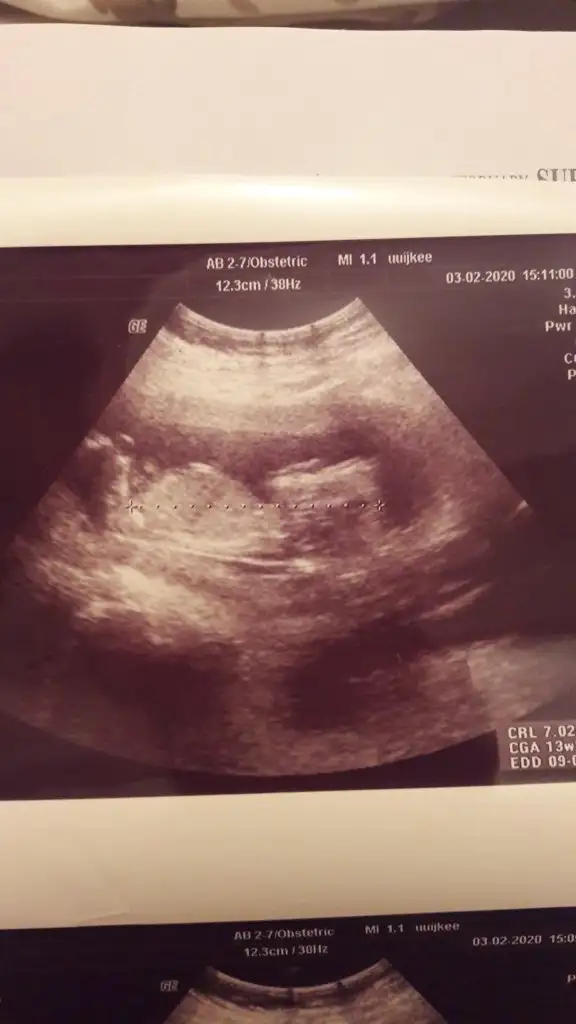

İkra meyra 12 haftalık ken tekrar foto atın demiştiniz burda 12+5 sizce cinsiyet ne ?

Eklentiler

• EDF88188-D37F-4A20-999C-B32BE1D02EF0.webp